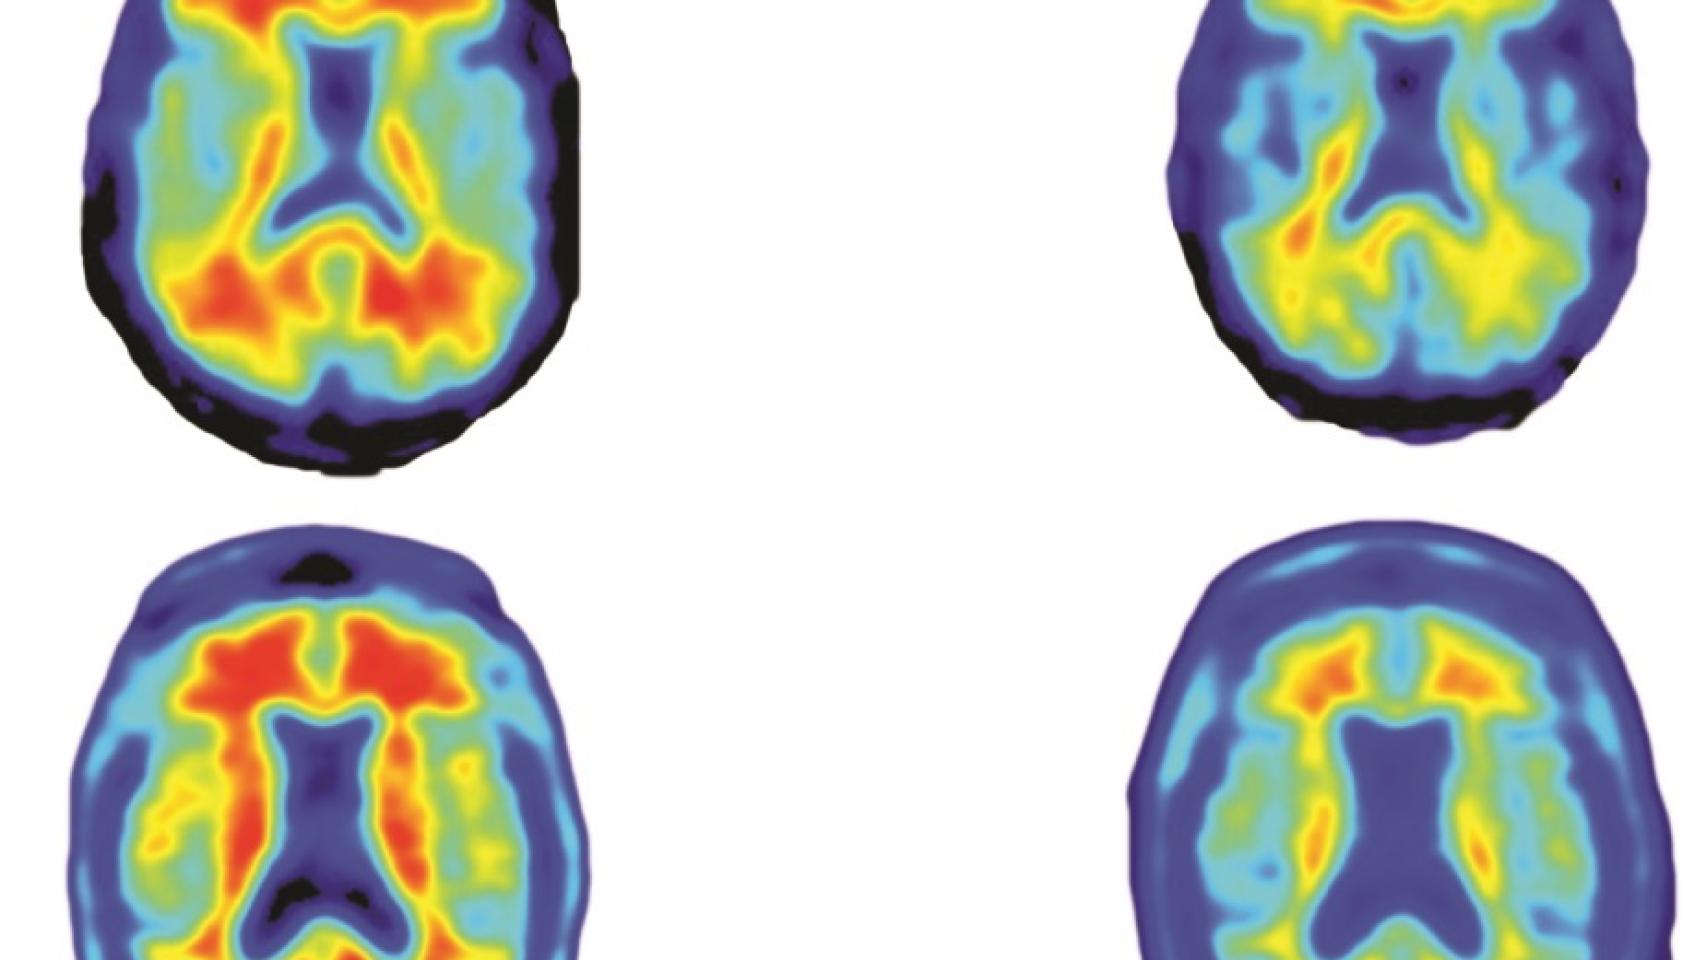

La acumulación de proteína beta amiloide es el desencadenante más conocido de los eventos cerebrales que llevan al alzhéimer, como se sospecha desde hace 25 años. En este cuarto de siglo no se ha conseguido evitar este fenómeno, que se visualiza fácilmente en pruebas de diagnóstico por imagen como el PET.

El estudio PRIME, que se publica esta semana pero que se presentó por primera vez el pasado año en una importante conferencia internacional sobre la enfermedad celebrada en Niza, no sólo demuestra que el fármaco reduce los depósitos de la proteína, sino que ralentiza el deterioro cognitivo asociado a esta patología. Eso es lo que realmente importa a médicos y pacientes, mucho más de los datos fríos de una prueba de diagnóstico por imagen.

Otro dato positivo es que se ha visto que la mejora va asociada a la dosis. Cuánto más medicamento recibieron los participantes asignados a tratamiento (que se dividieron en cuatro grupos según la cantidad inyectada) mayor fue la mejoría observada. De hecho, los 32 voluntarios a los que administró 10 miligramos por kilo de peso vieron sus depósitos reducidos casi a niveles previos al diagnóstico.